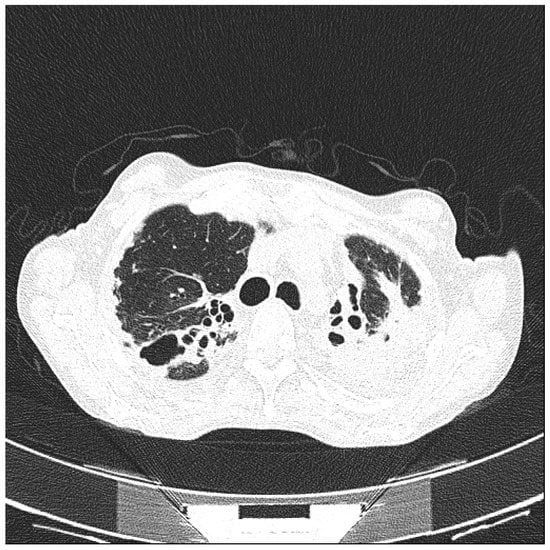

- Tokuda, H.; Sakai, F.; Yamada, H.; Johkoh, T.; Imamura, A.; Dohi, M.; Hirakata, M.; Yamada, T.; Kamatani, N.; Kikuchi, Y.; et al. Clinical and radiological features of Pneumocystis pneumonia in patients with rheumatoid arthritis, in comparison with methotrexate pneumonitis and Pneumocystis pneumonia in acquired immunodeficiency syndrome: A multicenter study. Intern. Med. 2008, 47, 915–923. [Google Scholar] [CrossRef] [PubMed]

- Mu, X.D.; Jia, P.; Gao, L.; Su, L.; Zhang, C.; Wang, R.G.; Wang, G.F. Relationship between Radiological Stages and Prognoses of Pneumocystis Pneumonia in Non-AIDS Immunocompromised Patients. Chin. Med. J. (Engl.) 2016, 129, 2020–2025. [Google Scholar] [CrossRef] [PubMed]

- Demirkazik, F.B.; Akin, A.; Uzun, O.; Akpinar, M.G.; Ariyürek, M.O. CT findings in immunocompromised patients with pulmonary infections. Diagn. Interv. Radiol. 2008, 14, 75–82. [Google Scholar] [PubMed]